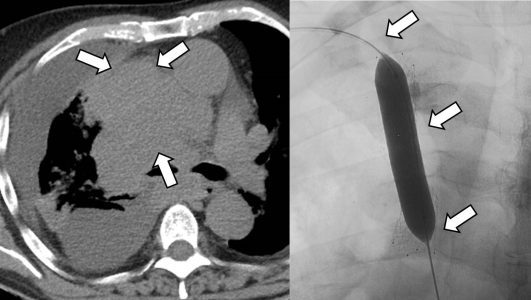

Ο χημειοεμβολισμός είναι μια επικουρική μέθοδος τοπικής θεραπείας για πρωτοπαθή και δευτεροπαθή νεοπλάσματα του ήπατος. Στόχος του επεμβατικού ακτινολόγου είναι η τοπική έγχυση χημειοθεραπευτικού σε κλάδους της ηπατικής αρτηρίας, ώστε να επιτευχθούν υψηλές συγκεντρώσεις τοπικά στην ηπατική εξεργασία χωρίς να προκαλούνται συστηματικές επιπλοκές τοξικότητας του χημειοθεραπευτικού. Επιπλέον, προκαλείται τοπική ισχαιμία-νέκρωση στην περιοχή του όγκου από τα εμβολικά υλικά-μικροσφαιρίδια εμβολισμού, χωρίς να επηρεάζεται το φυσιολογικό ηπατικό παρέγχυμα.

Ο χημειοεμβολισμός έχει καθιερωθεί ως θεραπεία εκλογής στην περίπτωση του ηπατοκυτταρικού καρκινώματος. Ενδείκνυται επίσης σε ηπατικές μεταστάσεις από νευροενδοκρινείς όγκους, καρκίνο παχέος εντέρου και μελάνωμα, σε συνδυασμό με συστηματική χημειοθεραπεία, της οποίας ενισχύει και βελτιώνει τα αποτελέσματα. Ενδείξεις αποτελούν επίσης το χολαγγειοκαρκίνωμα και οι μεταστάσεις από καρκίνωμα νεφρού και σαρκώματα μαλακών μορίων. Οι περισσότεροι ασθενείς μπορούν να επιστρέψουν στο σπίτι τους μία ημέρα μετά τη θεραπεία.

Υπερεκλεκτικός χημειοεμβολισμός πολυεστιακού ηπατοκυτταρικού καρκινώματος

Θεραπεία συνδρόμου άνω κοίλης φλέβας σε ασθενή με εκτεταμένο καρκίνο πνεύμονα